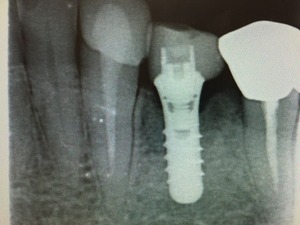

今回の症例はストローマンインプラントSLActiveで行った症例で骨が増えたものをお見せします。

このインプラントは不思議な特性があります。インプラントの周囲に最初は骨が少なくてもまとわりつくように増えるケースをいくつか経験しています。それゆえにロストした症例はいまのところ1つもありません。こんなインプラントならドクターも患者さんも安心ですね!